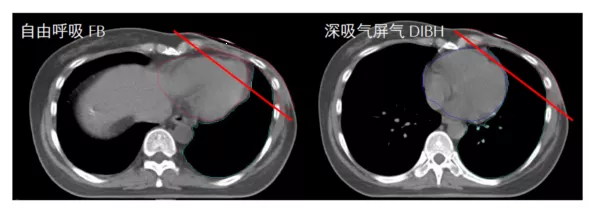

呼吸门控技术是近10年来在乳腺癌放疗领域的一个重大的技术变革。患者通过深吸气扩张肺组-织,将心脏从胸壁拉开(图1)。在屏住呼吸阶段,实施放射治疗。剂量学研究显示,跟自由呼吸状态相比,左侧乳腺癌患者可以有效的将心脏剂量降低约20-50%左右。在需要照射内乳淋巴结的时候,心脏剂量的降低更加明显。

图1